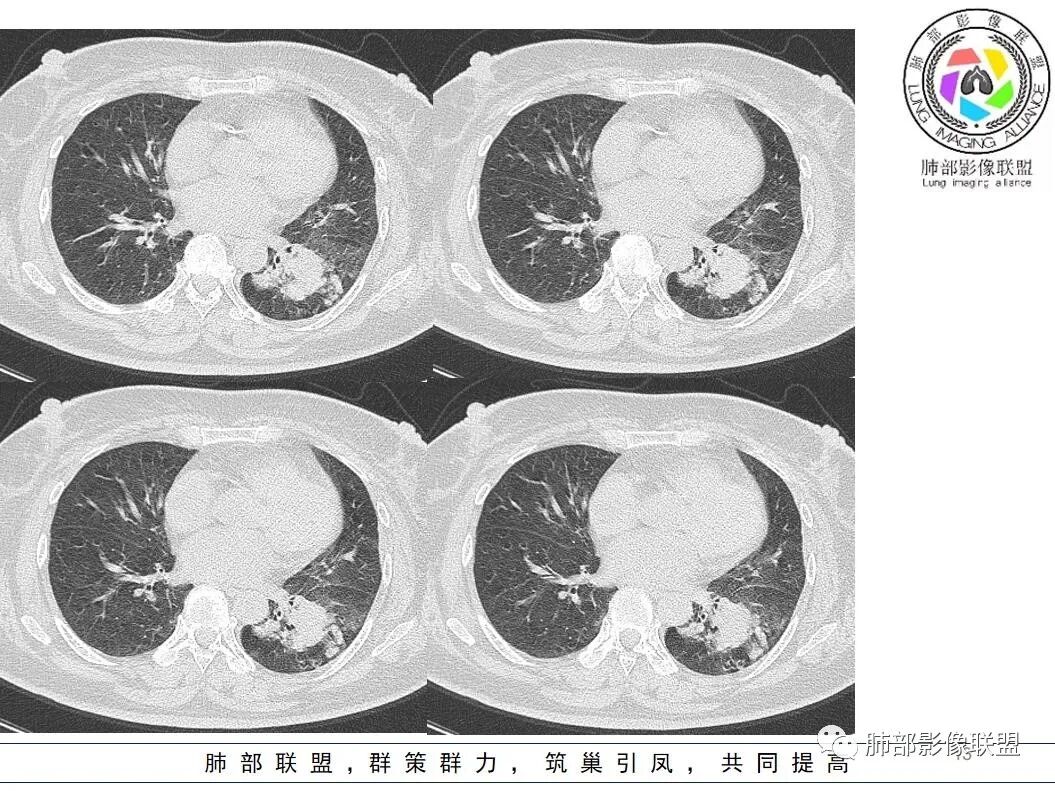

2. 影像表现:CT示左侧胸廓较对侧略塌陷,左肺下叶体积缩小,叶间裂略向左肺下叶轻度移位;双肺多发低密度空气潴留,以左肺下叶明显。左肺下叶团片状高密度影,可疑沿支气管血管束分布,病变近段支气管分支夹角增大,病变内见多支细支气管迂曲、牵拉扩张,部分细支气管达病变以远,病灶整体形态不规则,病变后内侧局部膨隆较明显,邻近叶间裂牵拉凹陷,图像伪影明显,病灶边缘可疑伴有磨玻璃晕等,邻近背侧胸膜多处增厚且范围较广;病变以远肺组织见局限性肺野透亮度增加,病变周围见多发实性结节;增强扫描病灶呈相对均匀强化。另左肺下叶部分支气管管壁增厚,局部肺野密度增高。病变部分边界清楚,局部可见月牙铲及胸膜凹陷征,胸膜牵拉僵直。

3.病例小结:本例外伤后意外发现,缺乏发热及呼吸系统相关临床表现,也没有提供相关的血常规、血沉、CRP、hs-CRP、降钙素原等炎性指标情况,不宜首先考虑普通感染性病变,但是此患者有糖尿病基础,灶周多发结节,因此结核等特殊感染需要排除,尽管缺乏典型树芽征。CT病灶抱团,膨隆感较明显,缺乏平直征、刀切征等,病灶周围可疑磨玻璃晕,增强相对均匀强化,该患者为老年无相关症状患者,恶性肿瘤要警惕,又是女性患者,加上胸膜凹陷征、扩张的充气支气管征等等,腺癌等恶性病灶应当重点鉴别,可惜缺乏既往影像资料对比。